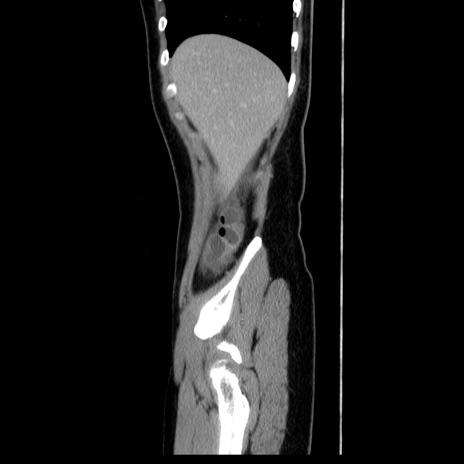

症例39(矢状断像)

【症例】40歳代女性

【主訴】上下腹部痛

【現病歴】2日目から下腹部痛あり。夜間は痛みで眠れなかった。昨日より上腹部痛と下痢が出現。臥位で痛みは軽快したため、休んでいた。本日になって臥位でも立位でも痛みが強くなってきたため救急要請。

【既往歴】子宮内膜症

【身体所見】部:平坦・軟、左上下腹部に圧痛あり、反跳痛あり。

【データ】WBC 21800、CRP 26.78

CT